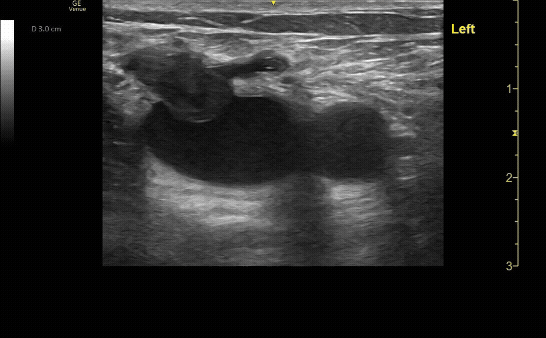

Positive DVT ultrasound showing clot, and incomplete compression at the junction of the greater sapphenous vein and femoral vein.

c/o Samson Frendo, MD

Positive DVT ultrasound showing the bifurcation of the popliteal vein with incomplete compression of the popliteal vein.

c/o Matthew Hughes, MD